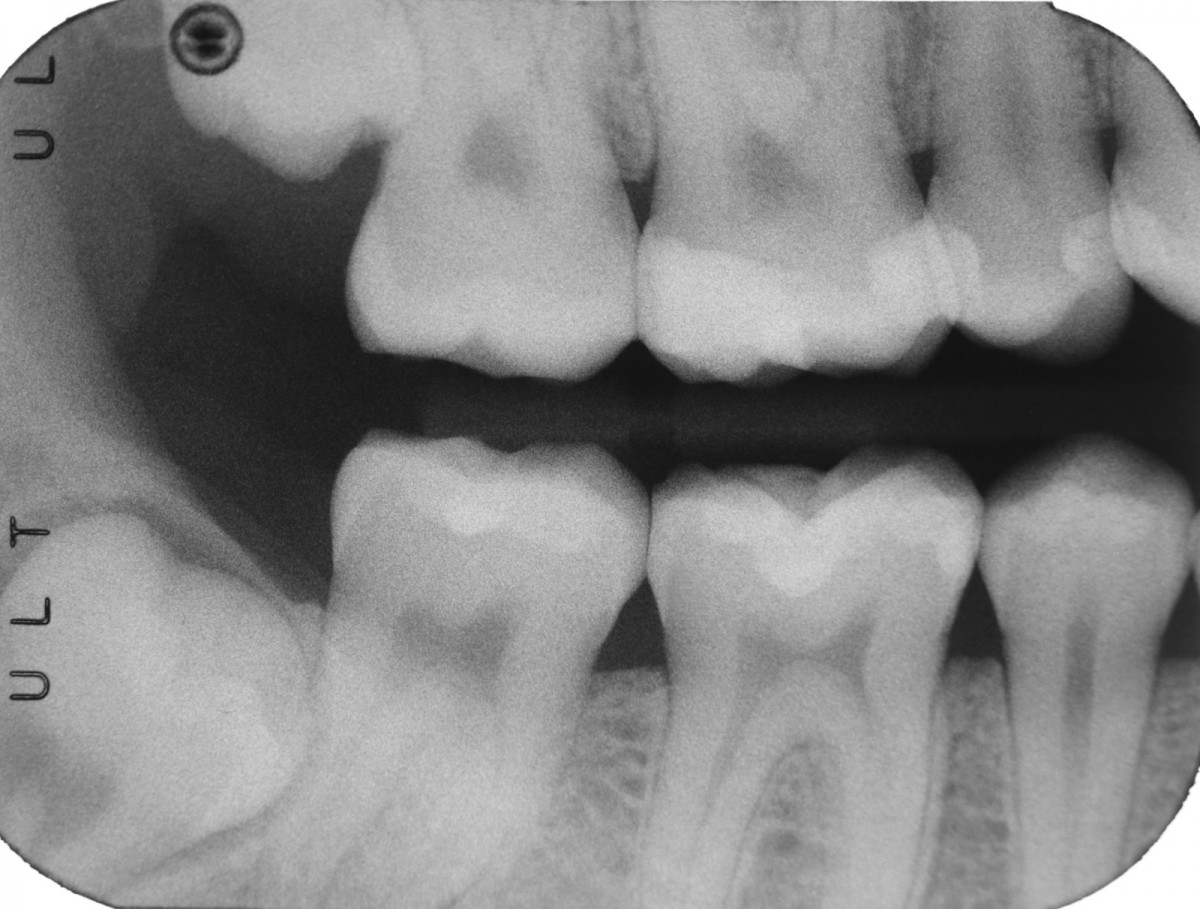

During the visit, consisting of the physical examination and instrumental examinations such as radiographs bitewings, thermal tests and compression tests (to exclude the presence of typical symptoms of a crack) at the level of the fourth quadrant, she has: amalgam restoration on dental element 4.6 associated with primary mesial caries and primary occlusal caries on 4.7.

The symptoms are not clearly identifiable by the patient but they can be traced back to dental elements 4.6 through diagnostic tests.